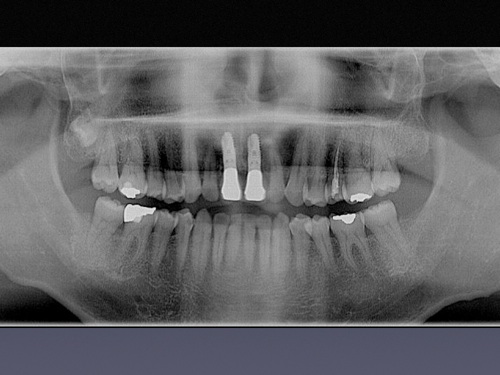

インプラント治療は、失われた歯牙を人工の歯根(チタン合金製)で再建する方法です。隣在する健康な歯を削ることが避けられる利点、かみ合わせの崩壊を防止できる利点、すでに崩壊したかみ合わせを回復できる利点、義歯の安定化が得られる利点、審美的な外観が得られる利点等、数々の利点を備えている、現在の歯科医療ではなくてならない極めて有用な治療法の一つです。

インプラント治療を安全に行うため、当院ではCT分析ソフト(SimPlant)を用い診断、シミュレーションを行っております。

以下の画像のように詳細な情報が得られることがお分かりいただけると思います。